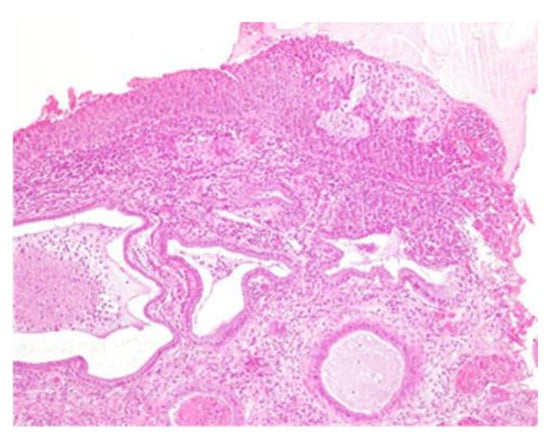

Figure 3.

Histological sample of the excised tissue representing the main portion of the excised cervix. Morphologically, enlarged and hyperchromatic nuclei, clumped chromatin, irregularities, notches in the nuclear membrane, and an altered nuclear/cytoplasmic ratio can be observed. The lesion appears extensive at the electroresorptive margins. The lesion is compatible with a diagnosis of CIN3, with an aggravation of the initial CIN2 pathology.